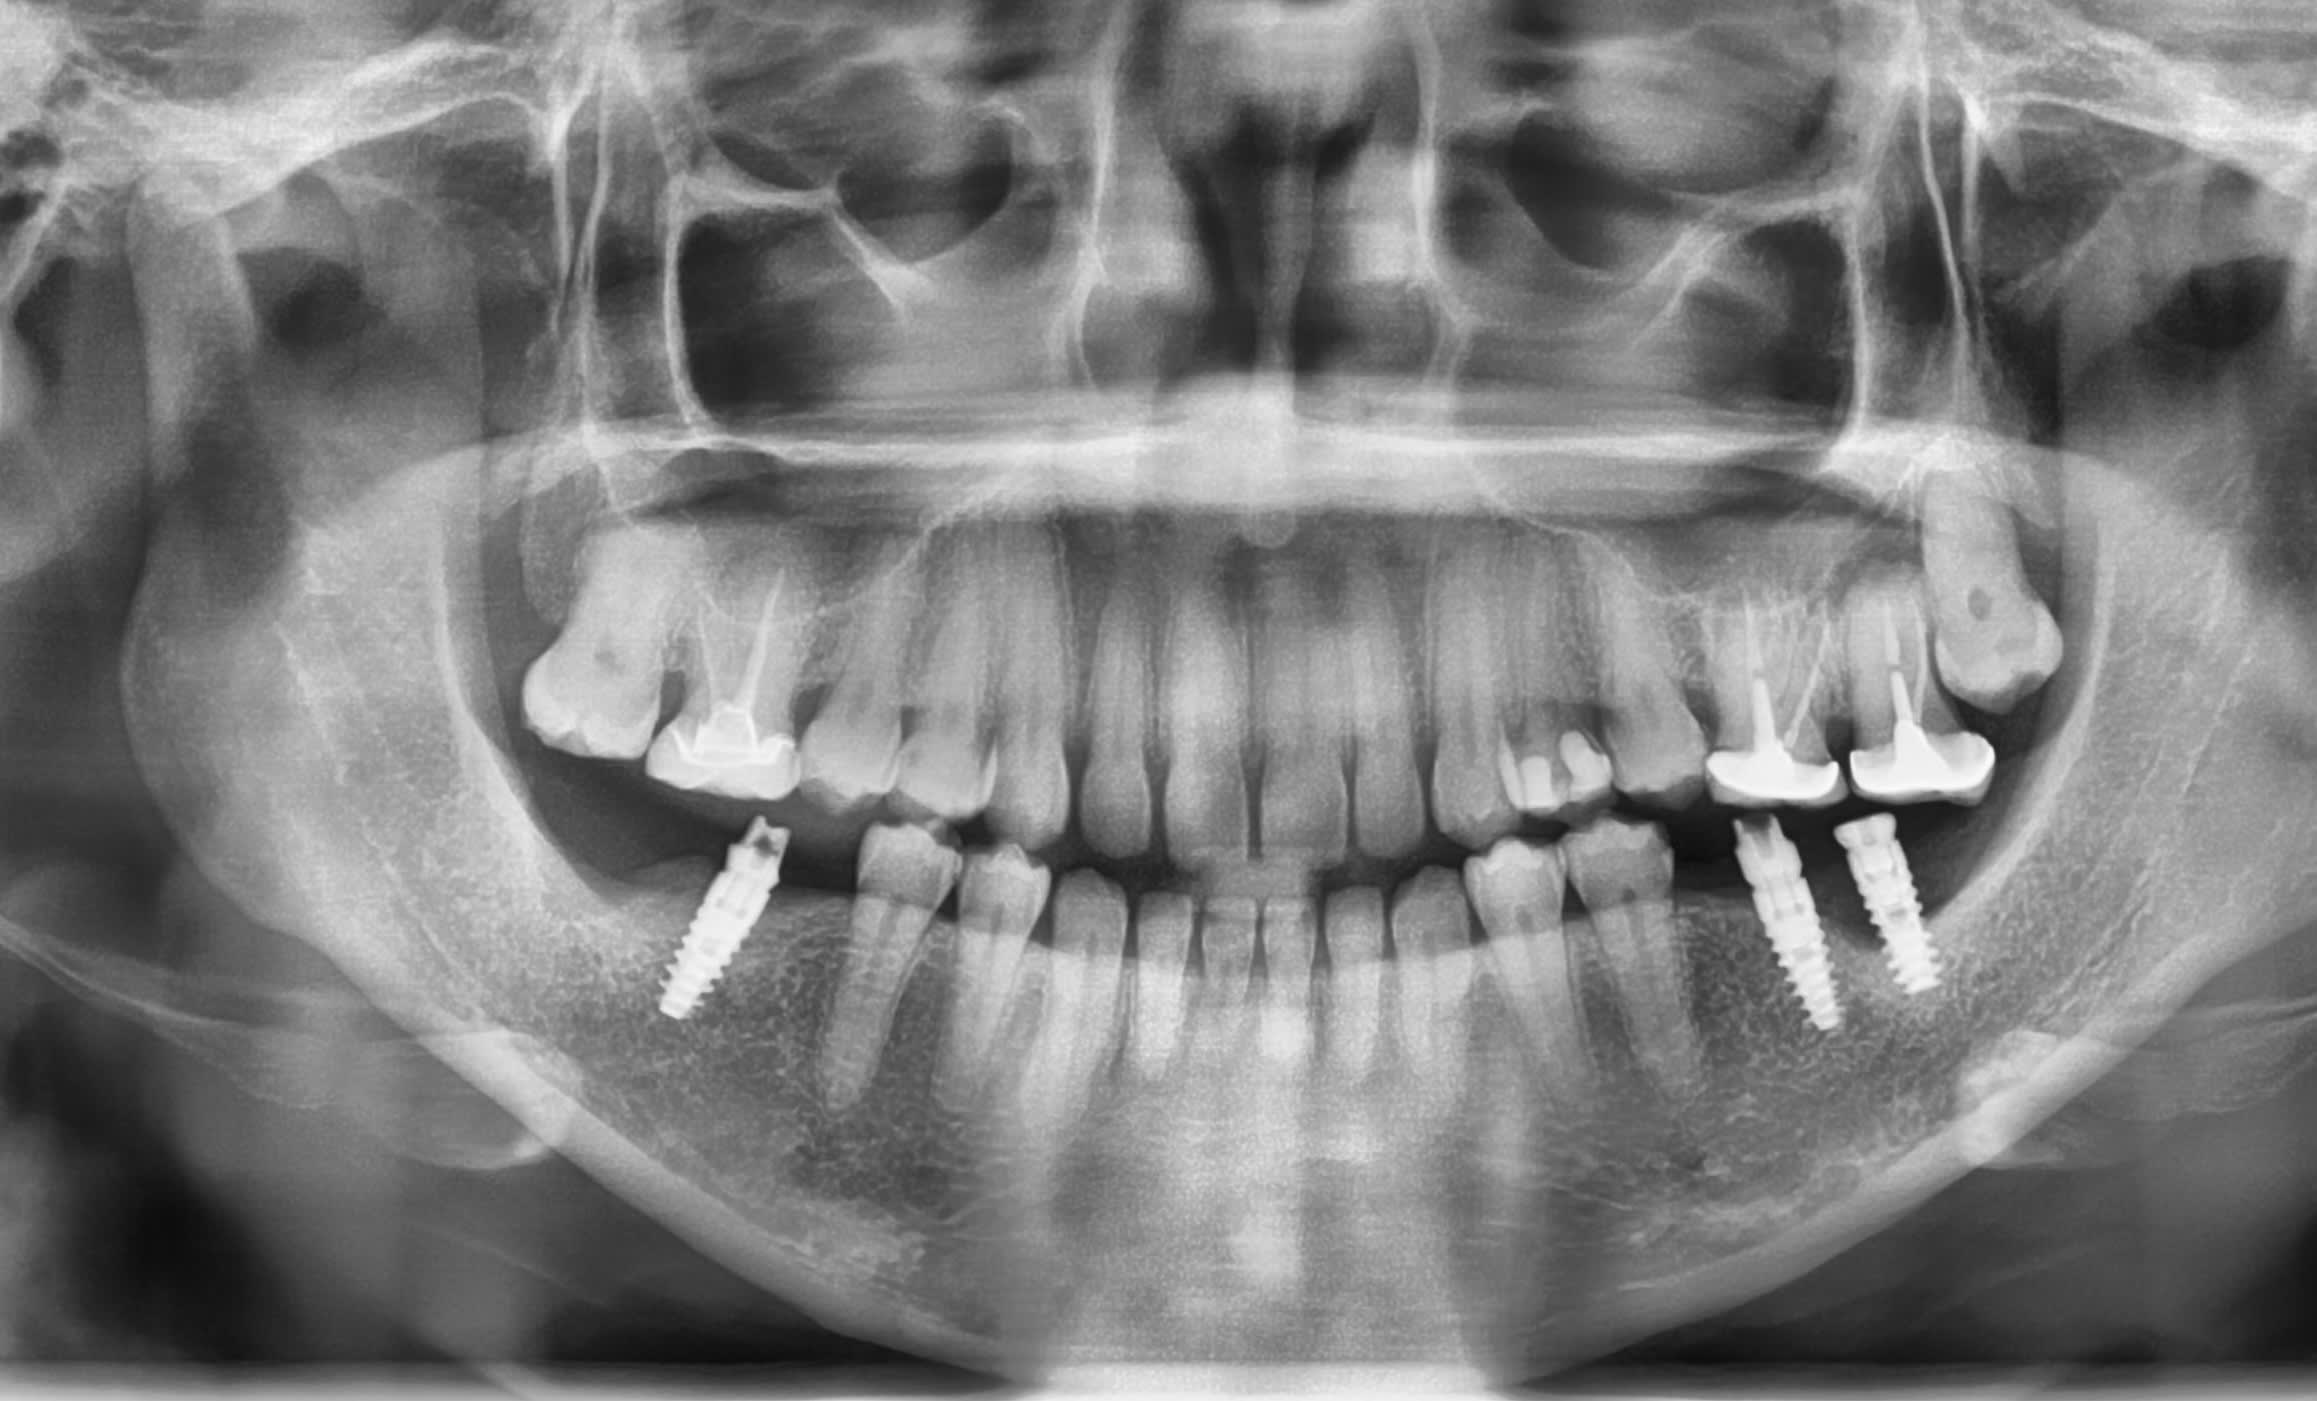

une petite aide sur l'identification de ces implants

Une patiente revenante, des implants et surement des dents à déposer.

je pensais à de l'alphabio mais pas de réponse des commerciaux.